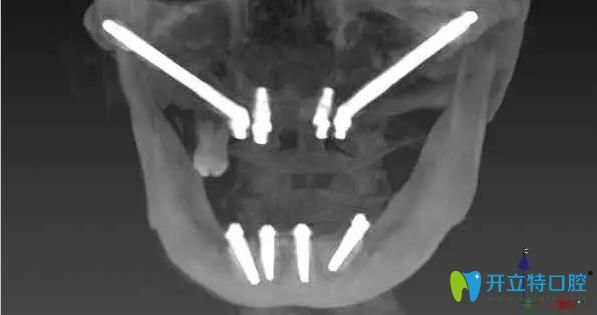

林阿姨,68歲,上下牙缺失多年,牙槽骨大量缺失,上頜竇氣化非常嚴重,前牙區(qū)的骨骼也特別窄、矮,做任何的修復都很困難,所以陳慧玲院長建議她做穿顴骨種植。

陳慧玲院長經(jīng)過詳細的術前檢查、做了充分的種植手術評估后,確定了種植方案。在多名醫(yī)生的共同努力下,利用穿顴種植+穿翼種植技術,用六顆種植體來進行上半口全固定修復,即刻種植、即刻修復。當天下午,林阿姨就戴上了固定臨時牙,回家就可以吃東西。